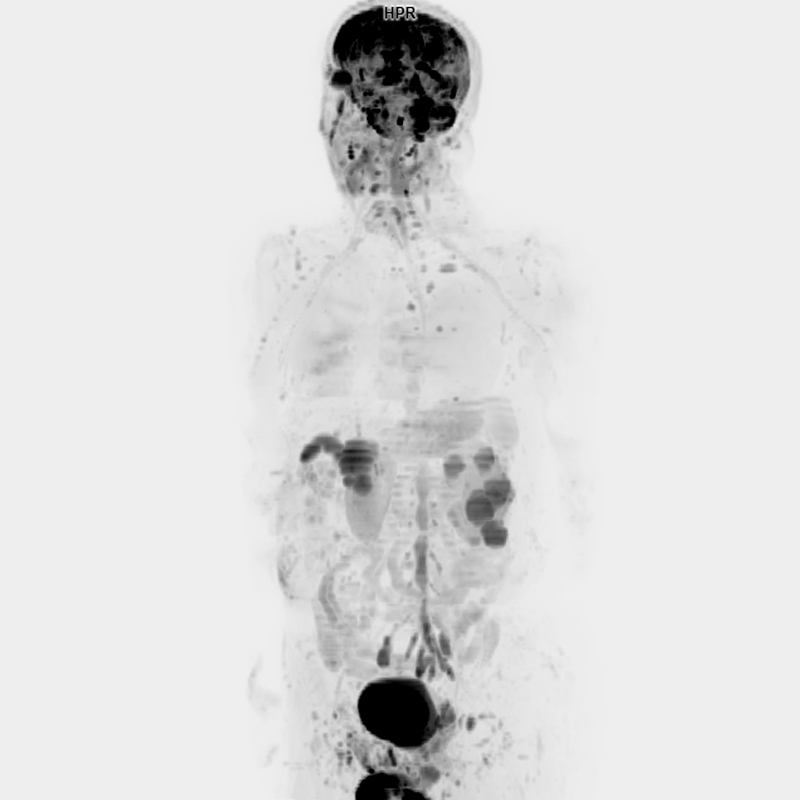

3 Tesla MR Tüm Vücut Görüntülemede Yapay Zeka Destekli Son Teknoloji